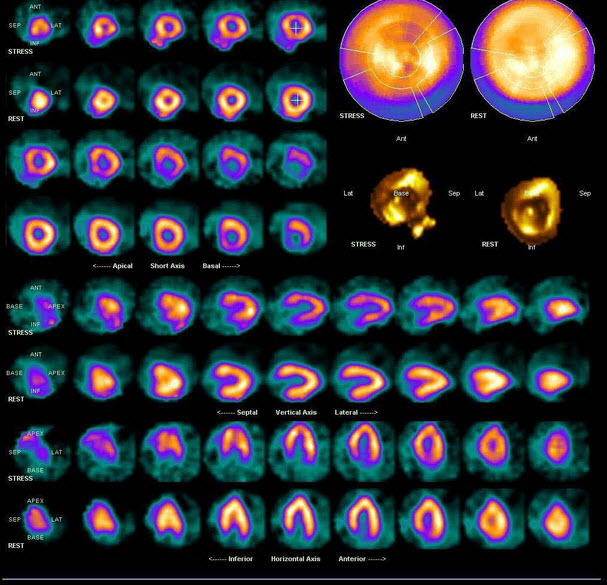

41、多项选择题

男,21岁,临床诊断胃癌,诉全身多处骨关节疼痛,行全身骨显像如图,对此影像下列描述正确的是()

A.胸12椎体放射性“冷区”

B.若同时X线检查为阴性则提示骨转移可能性大

C.“冷区”的出现一定表明骨转移

D.患者胸骨浓聚提示骨转移

E.胸12椎体可能存在肿瘤的骨髓浸润

点击查看答案